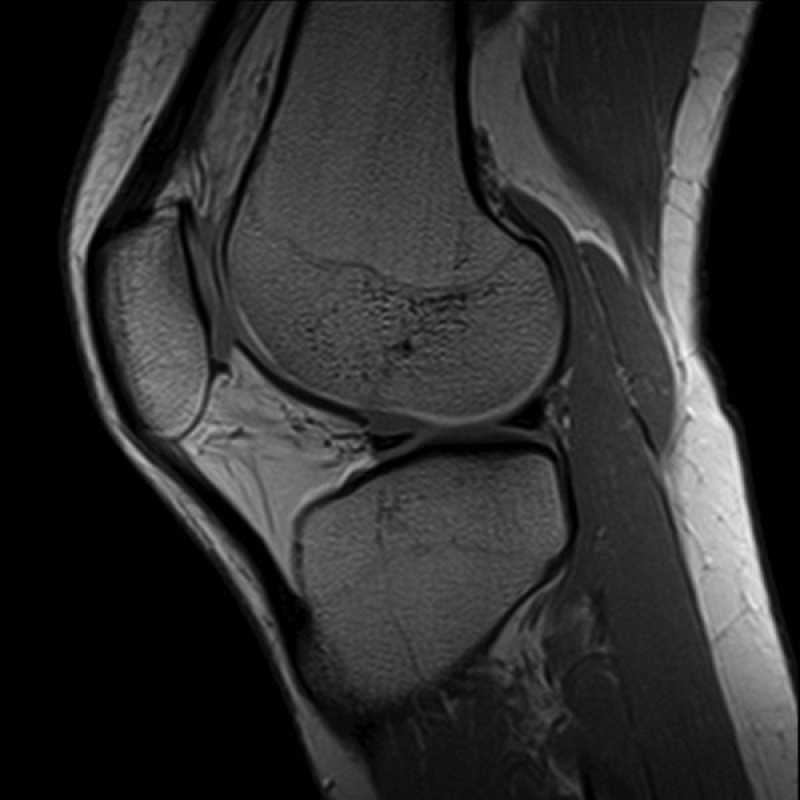

• Ressonância de joelho;